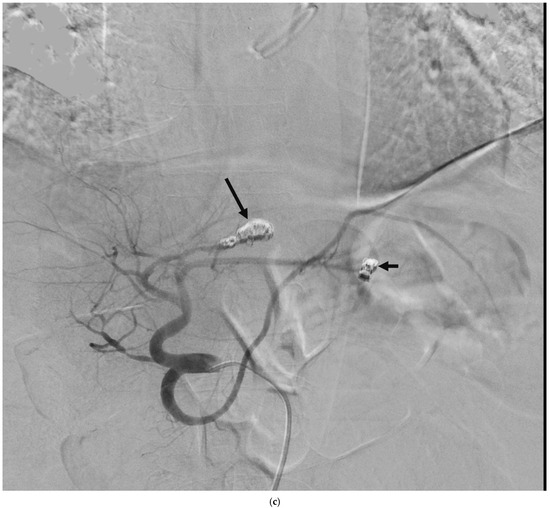

4.4. Treatment and Outcome